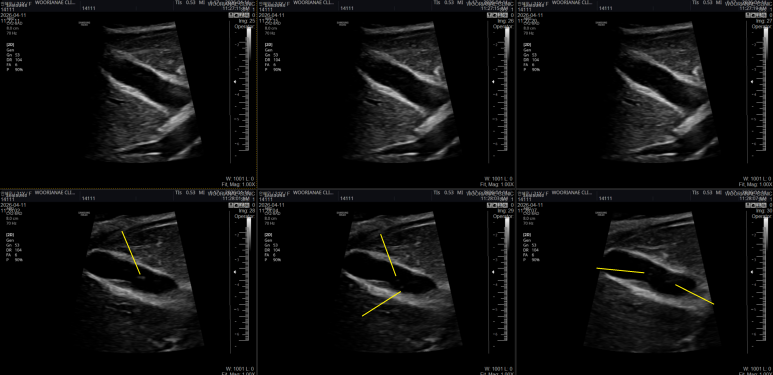

17년 갑상선 저하증 투약중인 환자 초음파 변화, 하시모토 갑상선염 - 동대문구 답십리, 전농동, 우리안애 우리안愛 내과

https://blog.naver.com/ejercicio/221539631275 상기 50대 초반 여자 20년과 26년 갑상선 모습의 변화 비교, 6년만의 갑상선 초음파 위축성 변화가 더욱 뚜렷해졌다. 75 ug으로 초기에 감량 후 변화없이 유지중 좌엽 아랫쪽 림프절은 커지지 않고 관찰된다. https://blog.naver.com/ejercicio/223829917553 동대문구 답십리 우리안애, 우리안愛 내과, 건강검진 클리닉 내과 전문의 전병연 #동대문구내과 #성동구내과 #광진구내과 #답십리역 #장안평역 #용답역 #청량리역 #신답역 #한양대역 #왕십리역 #답십리사거리 #촬영소사거리 #전농동사거리 #내과 #국가검진 #위내시경 #대장내시경 #갑상선초음파 #복부초음파 #경동맥초음파 #심장초음파 #암검진 #래미안위브아파트 #엘림스퀘어 #두산아파트 #동아아파